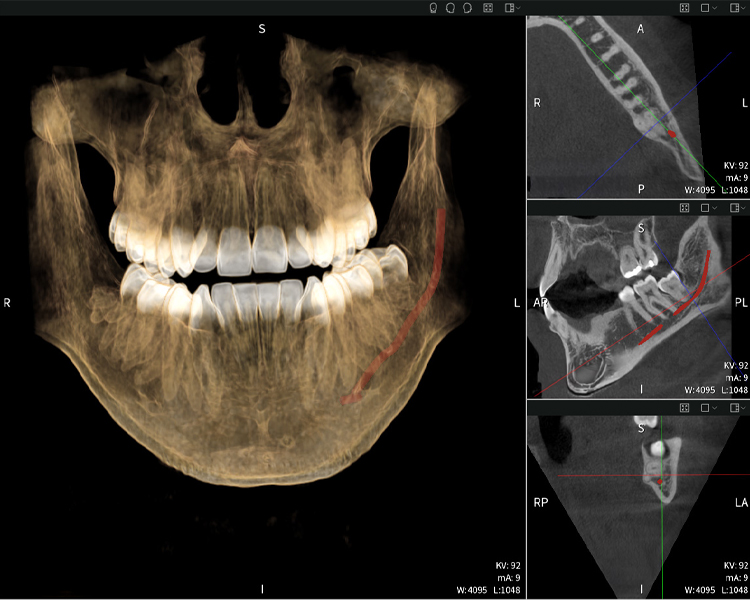

Abbildung d: Bildgebungsergebnisse von Seethrough Max vor einem schwarzen Hintergrund.

Abbildung d

Abbildungen b–d zeigen verschiedene Ansichten einer 3D-Rekonstruktion des Unterkiefers und bieten eine umfassende Übersicht über die Anatomie des Unterkiefers, die Lage der Nerven im Verhältnis zu den Zähnen und ermöglichen die Beurteilung der Zahnsymmetrie und Ausrichtung.

Abbildung d zeigt den bereits vorbehandelten Zahn 48, dessen Krone entfernt wurde und dessen Wurzeln nahe am Nerv belassen wurden, was das hohe Risiko einer Nervenschädigung verdeutlicht.